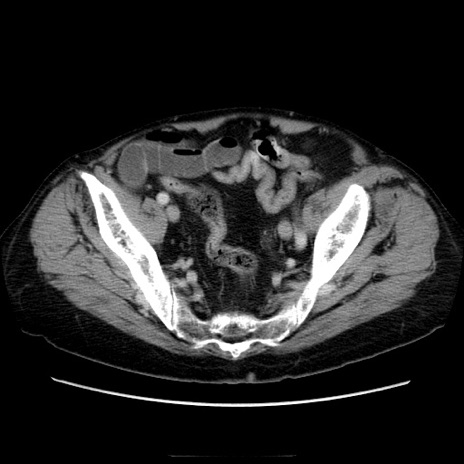

症例21(横断像)

【症例】70歳代男性

【主訴】腹痛

【現病歴】肝硬変・肝細胞癌にてかかりつけの方。約9時間前に食後より腹痛出現。症状が徐々に増悪し、嘔吐出現したため来院。

【既往歴】肝硬変、肝細胞癌(RFA、TACE後)

【身体所見】意識清明、表情苦悶様、BT 36℃、BP 129/78mmHg、P 88bpm、SpO2 97%(RA)、右上腹部から心窩部にかけて圧痛あり、反跳痛なし、筋性防御あり。

【データ】WBC 5800、CRP 0.16